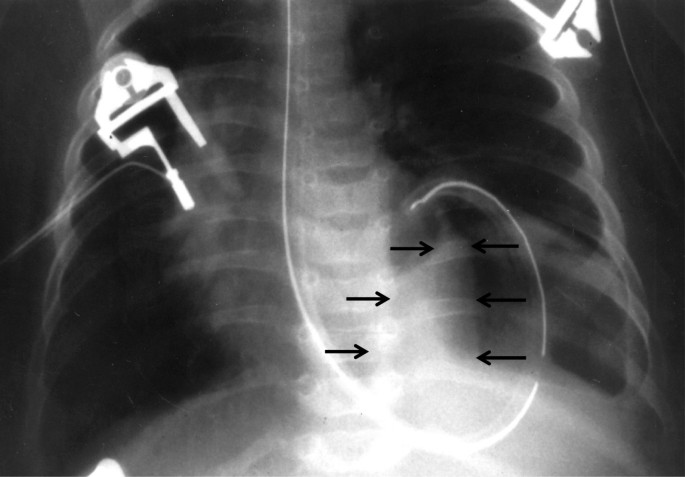

A 2,600 gram male was born at 37 weeks gestation with a diagnosis of left congenital diaphragmatic hernia made by prenatal ultrasonography. No other congenital abnormalities were found. The APGAR scores were 6 and 9 at 1 and 5 minutes, respectively. A frontal chest radiograph revealed the stomach in the left chest with shift of the mediastinum to the right. The heart was normal in shape and size. The left lobe of the liver was in the left chest (Figure 1). The child was stable at birth and continued to do well without cardiorespiratory support or evidence of right to left shunting hence he was operated upon on the first day of life. The hernia was approached via a left subcostal incision. Upon reduction of viscera a standard left Bochdalek diaphragmatic defect 2cm in diameter was noted. Primary repair of the defect was carried out easily without a patch and the abdomen was closed without creating a ventral hernia. Twenty four hours after surgery the infant began to require increasing respiratory and cardiac support. A chest radiograph revealed a massively widened mediastinum. The so called liver cut-off sign, in which the liver shadow is not visible to the left of the spine, was present but we missed it (Figure 2). The echocardiogram showed an effusion and a mass in the pericardium to the right of the heart. It was felt that the mass was probably an iatrogenic hematoma possibly due to the umbilical artery catheter. A computerized tomographic (CT) scan was carried out to better delineate it. The CT scan demonstrated the mass to have the same density as the liver (Figure 3). Since the diagnosis was in question the patient was re-operated through a right anterolateral thoracotomy to permit vascular or cardiac repair, if required. The pericardium was opened vertically, anterior to the right phrenic nerve. The defect in the central tendon had a well-defined tendinous margin circumferentially, the caudal pericardium was absent and there was no hernia sac. The herniated bare area of the liver was easily reduced from the thorax, however, the defect was large and it extended across to the left edge of the pericardium. Hence it was safer to repair the defect with a Gore-Tex patch (W.L.Gore & Associates, Flagstaff, AZ) attached to the abdominal surface of the diaphragm to avoid compressing the heart during the repair. This was achieved through a right subcostal incision (Figure 4). The patient had an uneventful post-operative course following the second operation.

Chest radiograph 24 hours after repair of Bochdalek hernia. The grossly widened mediastinum, consisting of the mass and the heart, occupies almost the entire thorax. Only the right lobe of the liver is seen in the abdomen (marked by black arrows). The nasogastric tube and umbilical artery catheter are in place.